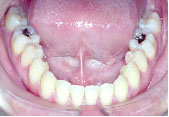

下の歯が上の歯より前に出て前歯は咬めていません。左上の第2小臼歯は骨の中に埋まっています。

また下あごは左にずれています。顎変形症、下顎前突と診断しました。